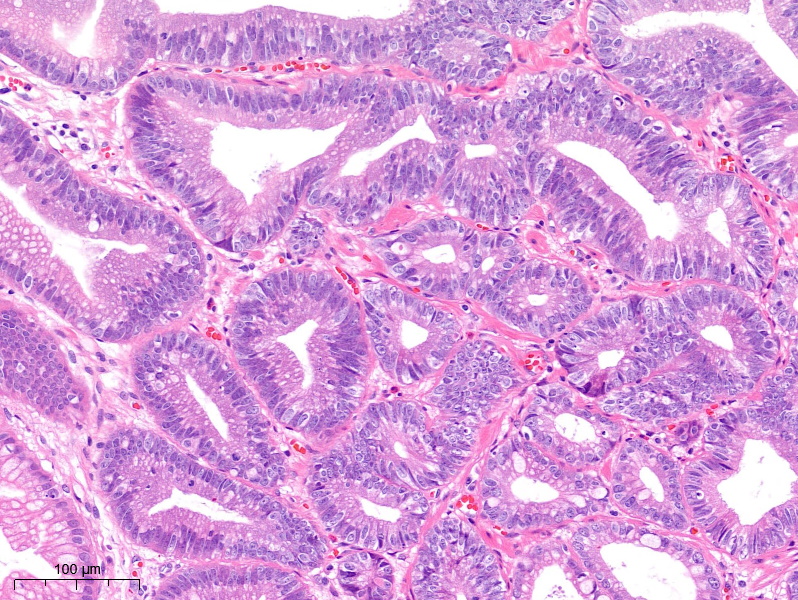

さて、病理の方ですが、

赤点と赤点の間に、癌腺管が確認できる範囲です。

癌の露出はなく、表層非腫瘍細胞で覆われている病変でした。

核の形状も類円形>紡錘形、重積が強く、高異型度高分化型腺癌(High grade)の診断としております。

今回、非常に珍しい、表層に癌細胞の露出を認めない隆起型の早期胃癌を経験しました。